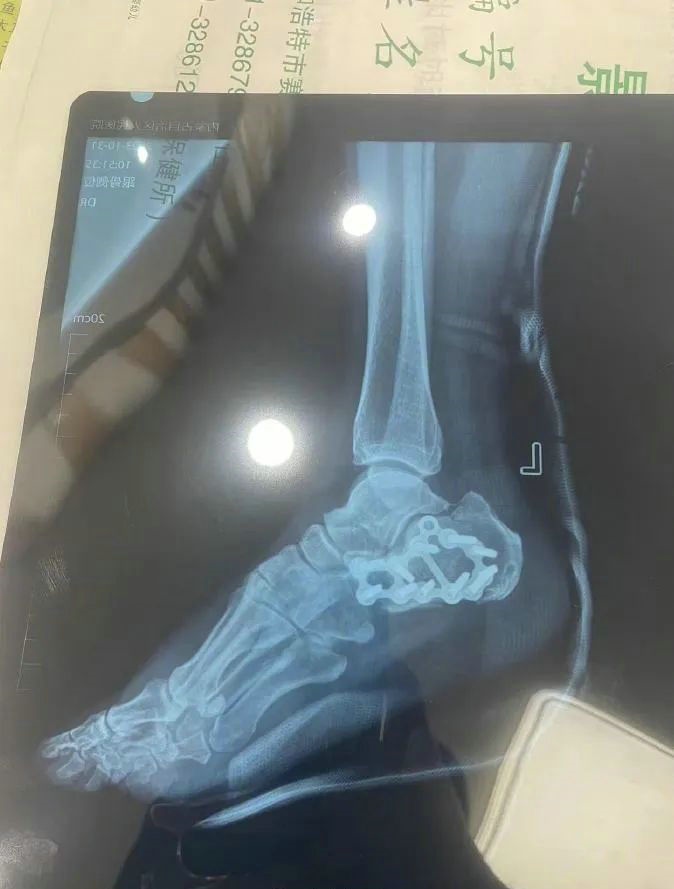

“那時候我剛工作了兩天,在第三天10月22日下午施工過程中從三層高的鐵架上摔了下來,導致30厘米左右的鋼筋刺穿我的右側(cè)臀部,左腳跟也粉碎性骨折,被送往內(nèi)蒙古自治區(qū)人民醫(yī)院救治,當晚做了手術(shù)取出刺在右臀部的鋼筋,10月30日又進行了左腳粉碎性骨折手術(shù)?!崩紫壬嬖V記者。